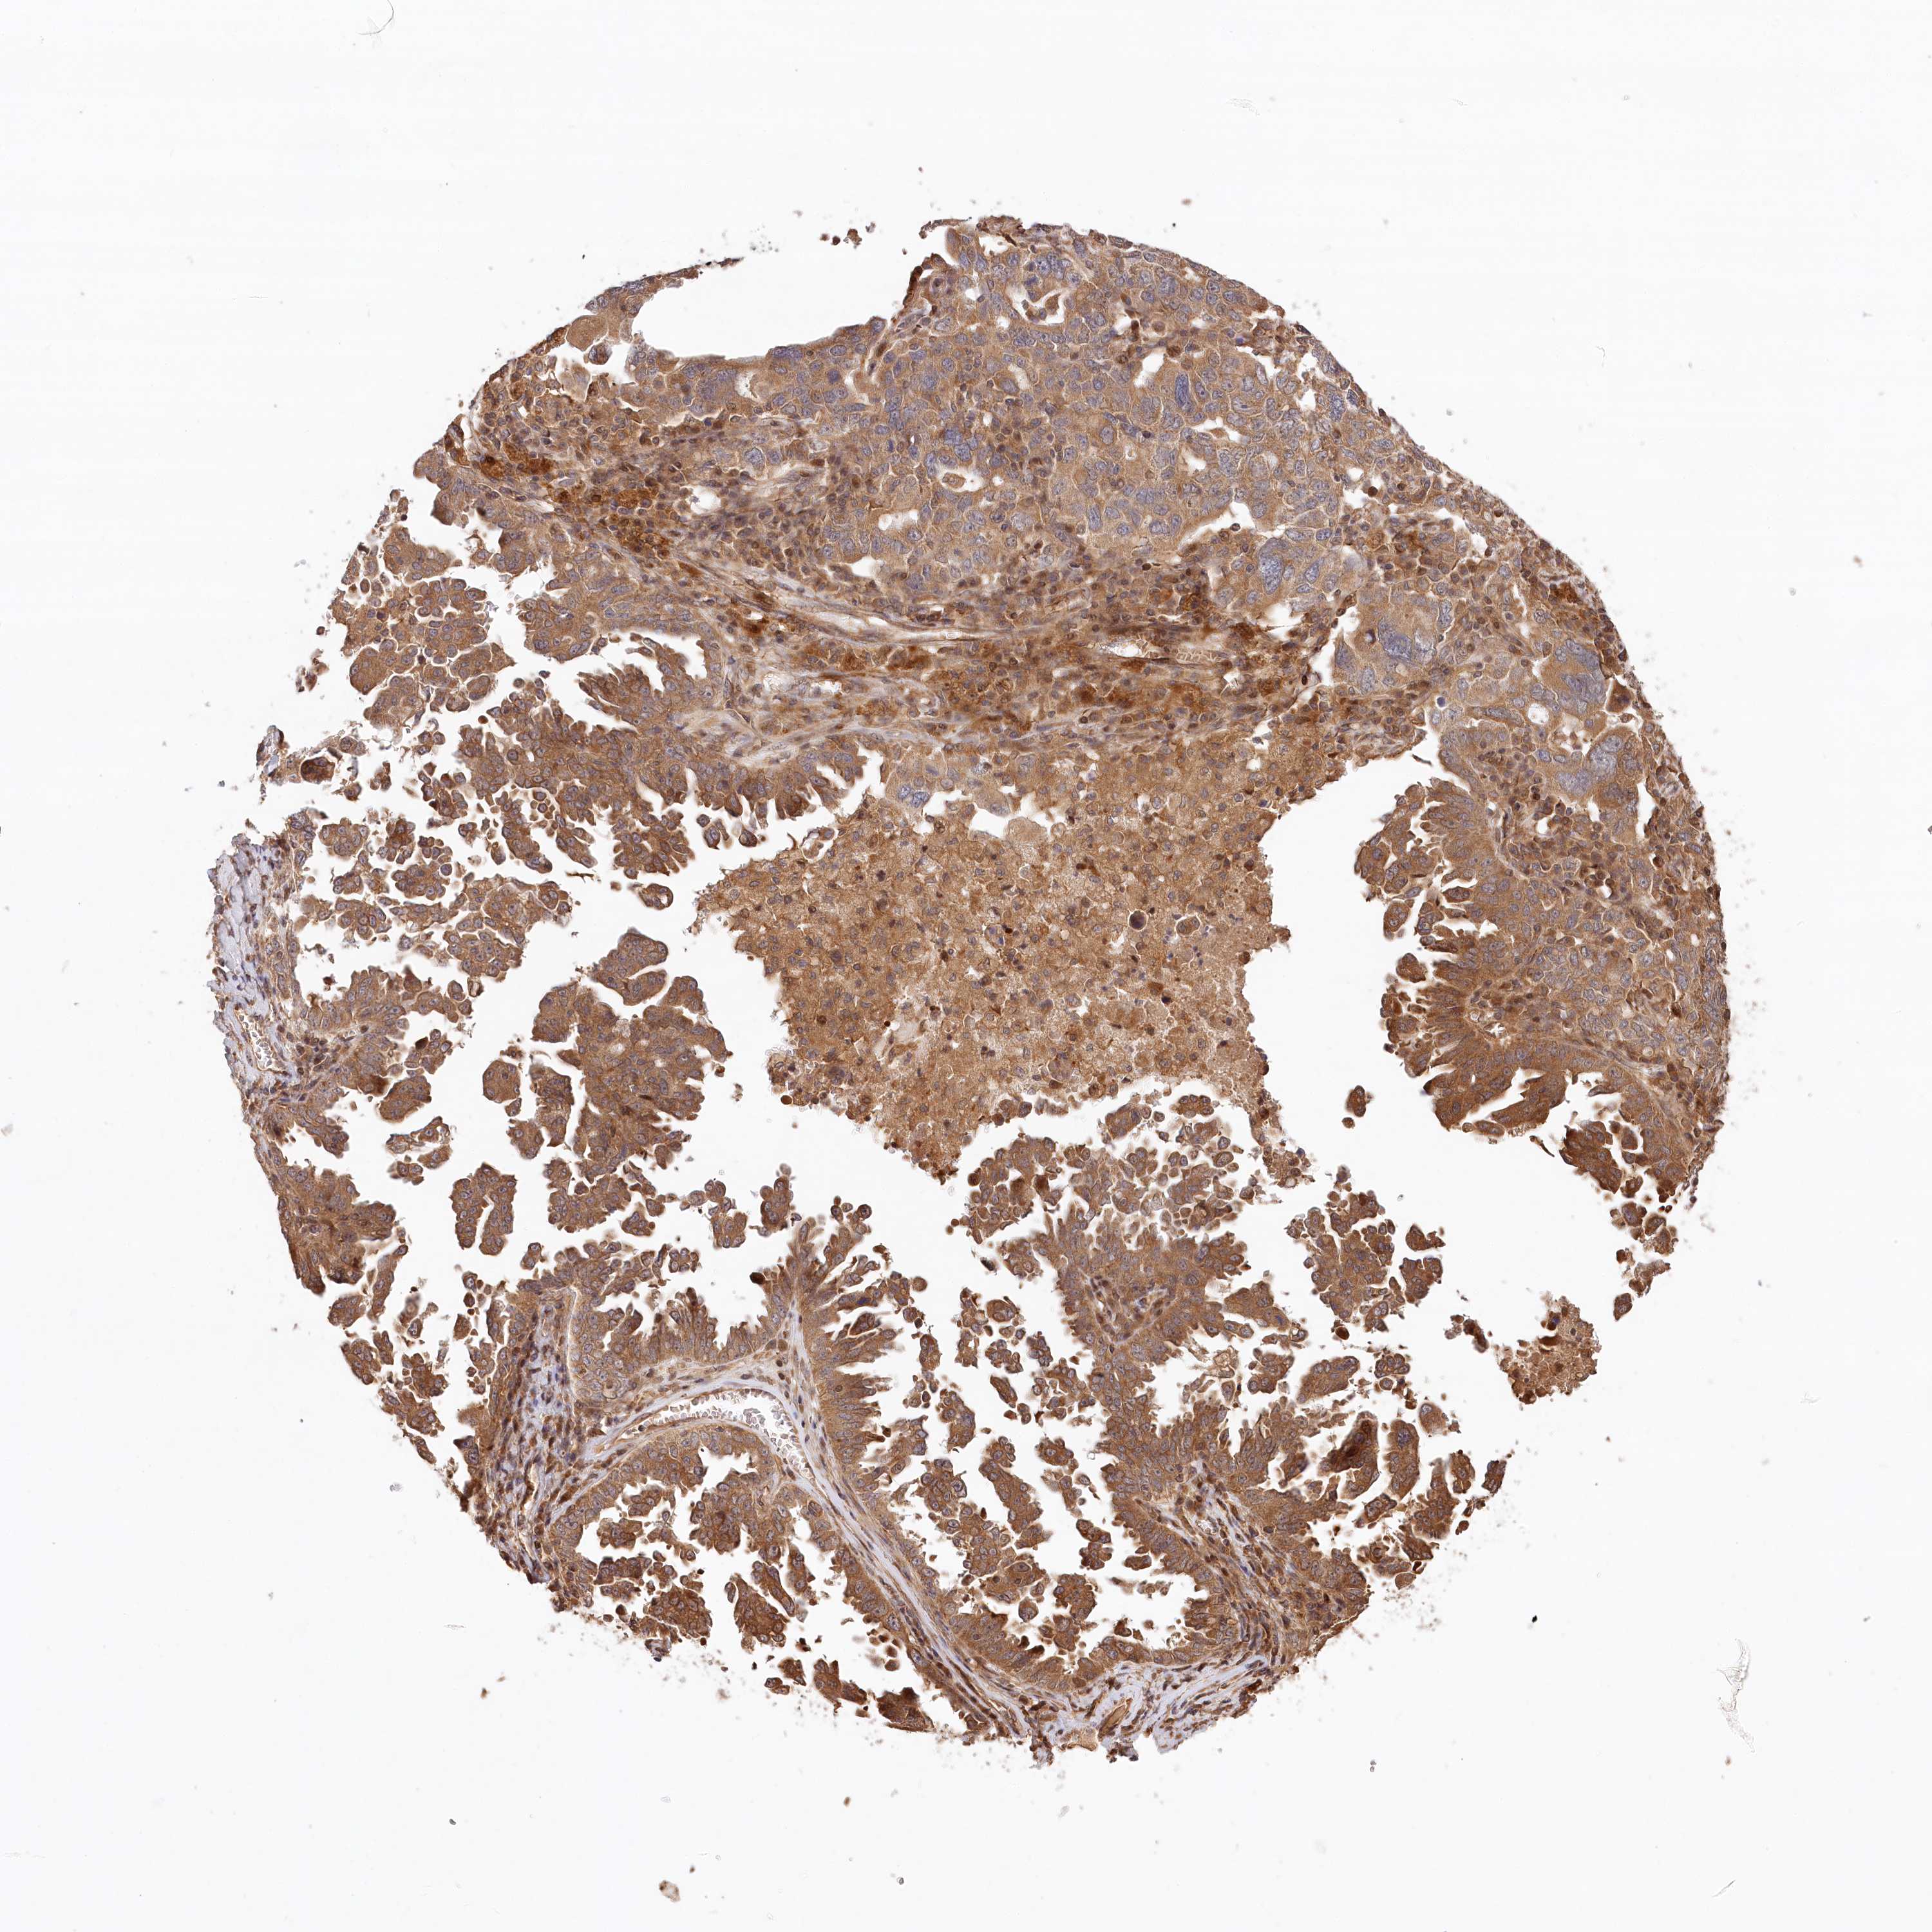

OVARIAN CANCER - Protein expressioni

A mouse-over function shows sample information and annotation data. Click on an image to view it in a full screen mode. Samples can be filtered based on level of antibody staining by selecting one or several of the following categories: high, medium, low and not detected. The assay and annotation is described here.

Note that samples used for immunohistochemistry by the Human Protein Atlas do not correspond to samples in the TCGA dataset.

Antibody stainingi

Antibody staining in the annotated cell types in the current human tissue is reported as not detected, low, medium, or high, based on conventional immunohistochemistry profiling in selected tissues. This score is based on the combination of the staining intensity and fraction of stained cells.

Each image is clickable and will lead to virtual microscopy that enables deeper exploration of all samples and also displays staining intensity scores, fraction scores and subcellular localization as well as patient and tissue information for each sample.

Antibody HPA032060

Antibody HPA032062

Antibody CAB034116

Staining

High

Medium

Low

Not detected

Intensity

Strong

Moderate

Weak

Negative

Quantity

>75%

75%-25%

<25%

None

Location

Nuclear

Cytoplasmic/membranous

Cytoplasmic/membranous,nuclear

Cystadenocarcinoma, serous, NOS

Carcinoma, endometroid

Cystadenocarcinoma, mucinous, NOS

Carcinoma, NOS